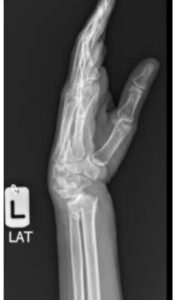

The distal radius is the end of the forearm bone closest to the wrist. A break in this area is called a distal radius fracture. It can range from a simple crack to a complex fracture involving joint surfaces.

- A visible deformity (crooked or bent wrist)

Dr. Ehab Aldlyami conducts a thorough clinical assessment and uses imaging tools such as X-rays and CT scans to determine: